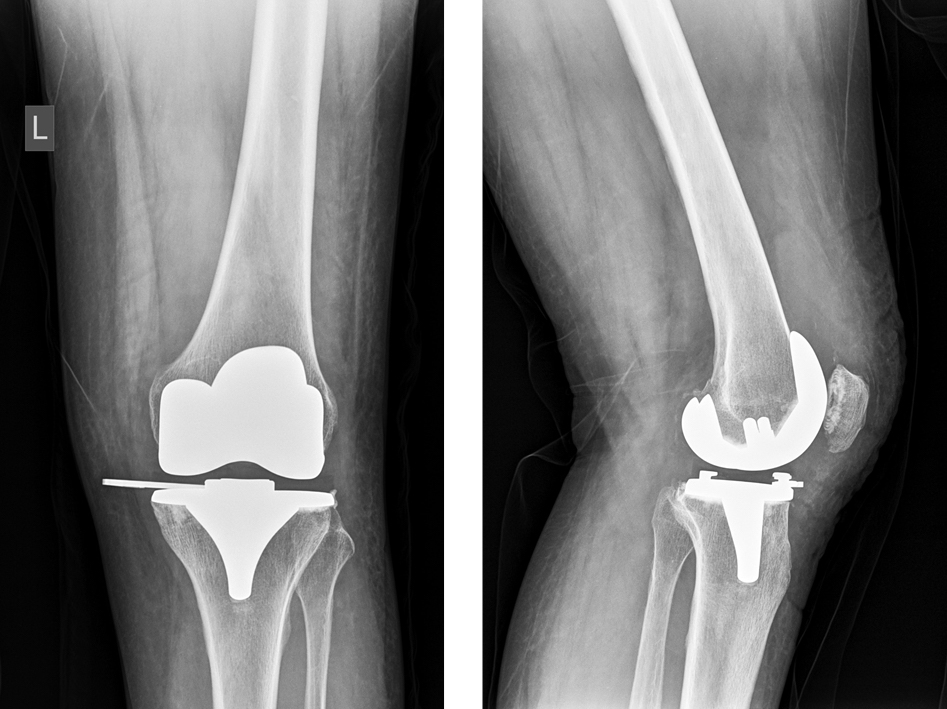

В день обращения пациентке выполнили предоперационную подготовку и провели экстренное хирургическое ревизионное вмешательство с заменой всего модуля (полиэтиленового вкладыша и его металлического фиксатора) на новый (рис. 4). Ревизия коленного сустава не выявила иных повреждений, признаков некорректной фиксации вкладыша, мягкотканного импинджмента, фронтальной или сагиттальной нестабильности протезированного коленного сустава, симптома «открытой книги» или иных проблем, способных быть очевидной причиной развившегося осложнения.

Рис. 4. Рентгенограммы коленного сустава после ревизионной операции

Fig. 4. Knee X-rays after revision surgery

При осмотре эксплантированного вкладыша и его фиксатора не выявлено их повреждений или производственных дефектов. Удаленный модуль был передан представителям фирмы Zimmer Biomet, и его изучение экспертами-технологами не выявило признаков производственного брака или механических повреждений фиксирующей системы. Течение послеоперационного периода было неосложненным, пациентка прошла курс реабилитационного лечения и закончила лечение с удовлетворительным функциональным результатом.